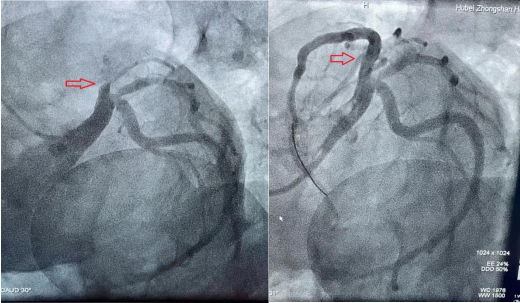

血管开通前 血管开通后

在患者家属手术签字后,心血管内科介入导管室启动,介入团队成员在20分钟内就到达导管室,并做好术前准备。患者被送入导管室,6分钟完成心血管冠脉造影,发现导致雷先生发病的前降支血管已完全闭塞了,此时雷先生真的是命悬一“管”啊。在征得家属同意后,心血管内科副主任李昌仅用5分钟左右的时间就开通了雷先生的“罪犯”血管,给雷先生开启了一条生命通道。一场争分夺秒的生死赛跑终于结束,雷先生的命保住了。此时,从雷先生进医院大门到血管开通仅仅才过去一个多小时,时间就是心肌,时间就是生命!